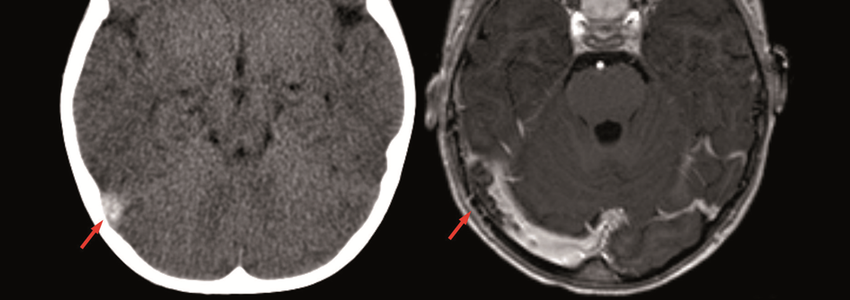

Post-Infarkt-Management

Eine große Beobachtungsstudie stellt die Routinegabe von Betablockern nach Herzinfarkt infrage: Nach Anpassung aller Einflussfaktoren fand sich kein…